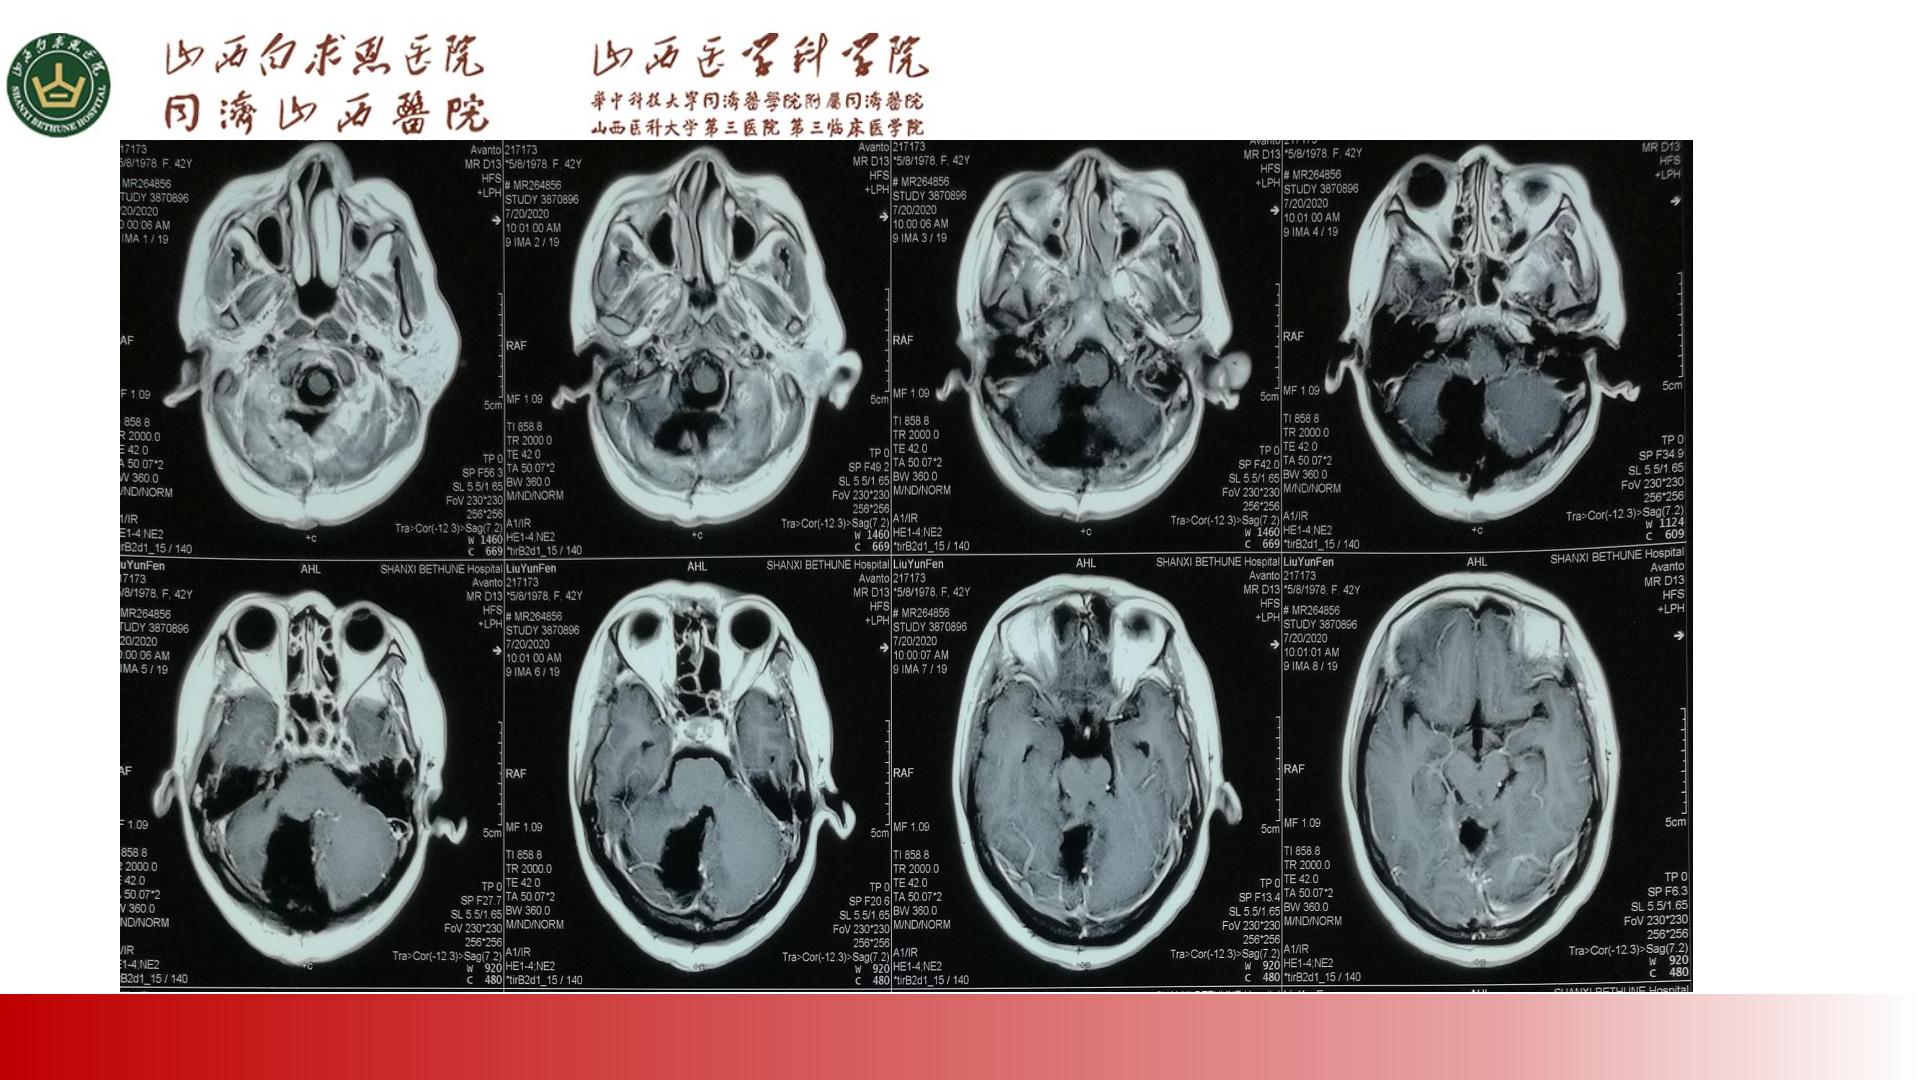

PPT:两例小脑节细胞胶质瘤治疗体会